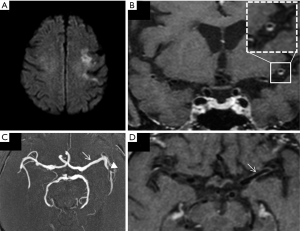

The MR imaging diagnosis relies on both the detection of vascular stenosis by 3D time of flight MRA and circumferential enhancement on VW-MRI (28). The enhancement can be either pencil-thin or thick, extending beyond the margin of the vessel wall (11,12). One or multiple stenoses can be identified, and their detection can be sensitized by the presence of circumferential enhancement on VW-MRI. The ability of vascular MR imaging to identify vasculitis relates to the size of the affected vessels (29).

Proximal involvement has been observed (30) in sarcoid, giant cell arteritis (GCA), systemic sclerosis, primary angiitis of the central nervous system, and infectious disease, foremost among which is Varicella Zoster vasculitis (Figure 2), frequently affecting M1 segment, responsible of basal ganglia infarcts. This can occur after primary or reactivated Varicella Zoster virus infection and in patients who are immunocompetent or immunosuppressed (31). Other infectious vasculitis etiologies are bacterial meningitis by pneumococcus and meningococcus, tuberculosis, Treponema pallidum, Borrelia burgdorferi, and fungus (27).